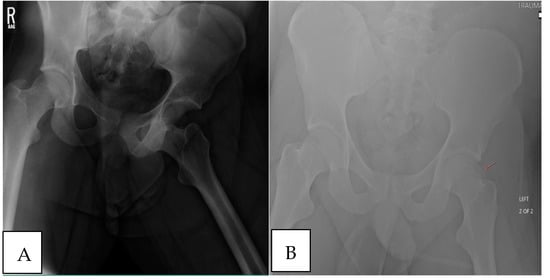

The patient was taken to the operating room for open reduction internal fixation (ORIF) of the left femoral head. They were positioned in the right lateral recumbent position for a posterolateral (Gibson) approach to the hip for digastric osteotomy and surgical dislocation. Following dissection through the soft tissue, a digastric trochanteric osteotomy was performed to preserve the short external rotators, piriformis, and vasculature of the femoral neck. A capsulotomy was performed, and upon dislocation of the left hip, a 5 × 4 cm impacted lesion of the femoral head was identified. There was a small piece of the weightbearing surface still intact, but the majority was traumatized, impacted, and unidentifiable (Figure 2A). The inferior portion of the weight–bearing surface was repaired with two 2.5 mm headless compression screws sunk underneath the articular surface (Figure 2B). Titanium screws were selected for increased fragment compression into the defect and more rigid fixation in comparison to bioabsorbable screws, as the fragment was located directly within the weight–bearing zone. The remaining defect was debrided to provide an appropriate surface for OAT. Two fresh-frozen proximal humerus allograft plugs (22 × 8 mm, 15 × 9 mm) were prepared with the Arthrex Osteochondral Autograft Transfer System (OATS; Athrex, Naples, FL, USA) (Figure 2C) following the measuring of the residual defect. Kirschner wires were placed and reamed over to deepen the recipient site for plug placement. The larger 22 mm plug was placed centrally into the weight–bearing dome, and a 15 mm plug was placed laterally on the femoral head (Figure 2D). The proximal humerus OAT plugs increased the weight–bearing zone neighboring the residual fragment but were not oversized to create a large deviation in the curvature of the articular surface. Therefore, Allosync Demineralized Bone Matrix (Arthrex, Naples, FL, USA) was introduced into the transplantation site to provide an osteoconductive matrix in unfilled areas surrounding the OAT plugs. The hip was reduced, and the capsule was repaired. The trochanteric osteotomy was repaired with two 4.5 mm cortical screws. Final imaging was obtained (Figure 3A). The patient was discharged to an inpatient rehabilitation facility for skilled nursing care and physical therapy. The patient remained non-weight–bearing for 8 weeks with early range of motion and presented for follow-up visitation at 2, 8, and 16 weeks postoperatively.

Figure 2. Intraoperative images of the large osteochondral defect and the definitive osteochondral allograft transplant. (A) The 5 × 4 cm impacted osteochondral lesion of the femoral head with a small surface of the weightbearing surface intact superior to the fovea. (B) Reduction and fixation of the inferior portion of the weight–bearing surface with two 2.5 mm headless compression screws. (C) Surface area demonstration of the proximal humerus osteochondral allograft (OAT) plug. (D) Placement of the 22 × 8 and 15 × 9 mm OAT plugs.